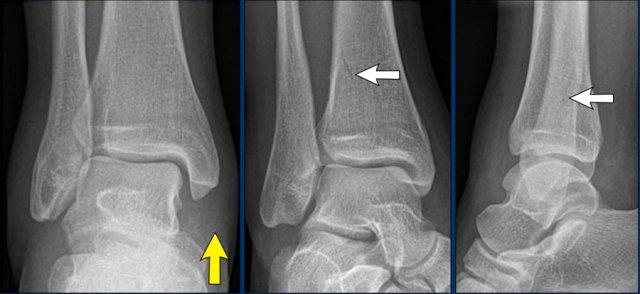

case 4 – distortion

Điều duy nhất chúng tôi nhận thấy là sưng nề mô mềm, đặc biệt ở phía trong.

Continue with the ankle injury algoritm…

Tổn thương các bó dây chằng bên trong có thể gặp trong gãy xương Weber B giai đoạn 4.

Tuy nhiên không có dấu hiệu của gãy xương Weber B.

Khả năng khác là có gãy xương Weber C kèm gãy xương mác cao, không hiển thị trên phim X-quang cổ chân.

Đứt dây chằng delta là giai đoạn 1 và tổn thương có thể dừng lại ở đó hoặc tiến triển đến giai đoạn 2, 3 hoặc thậm chí giai đoạn 4.

Chúng ta cần chụp thêm X-quang toàn bộ cẳng chân để xác định chúng ta đang đối mặt với giai đoạn nào.

Continue with the x-rays of the lower leg…

Có thể thấy gãy xương mác cao (Maisonneuve).

Thông thường bệnh nhân chỉ cảm thấy đau ở vùng cổ chân do đứt dây chằng rất đau và không chú ý đến gãy xương mác.